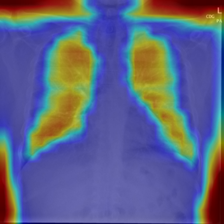

4.7.2 Activation Response Maps

As shown in Fig. 9, given the text lungs, we can find that the activation maps can accurately highlight the target regions. Therefore, we can achieve a higher performance on the downstream tasks. However, the activation maps are imperfect, as the background regions are also highlighted.